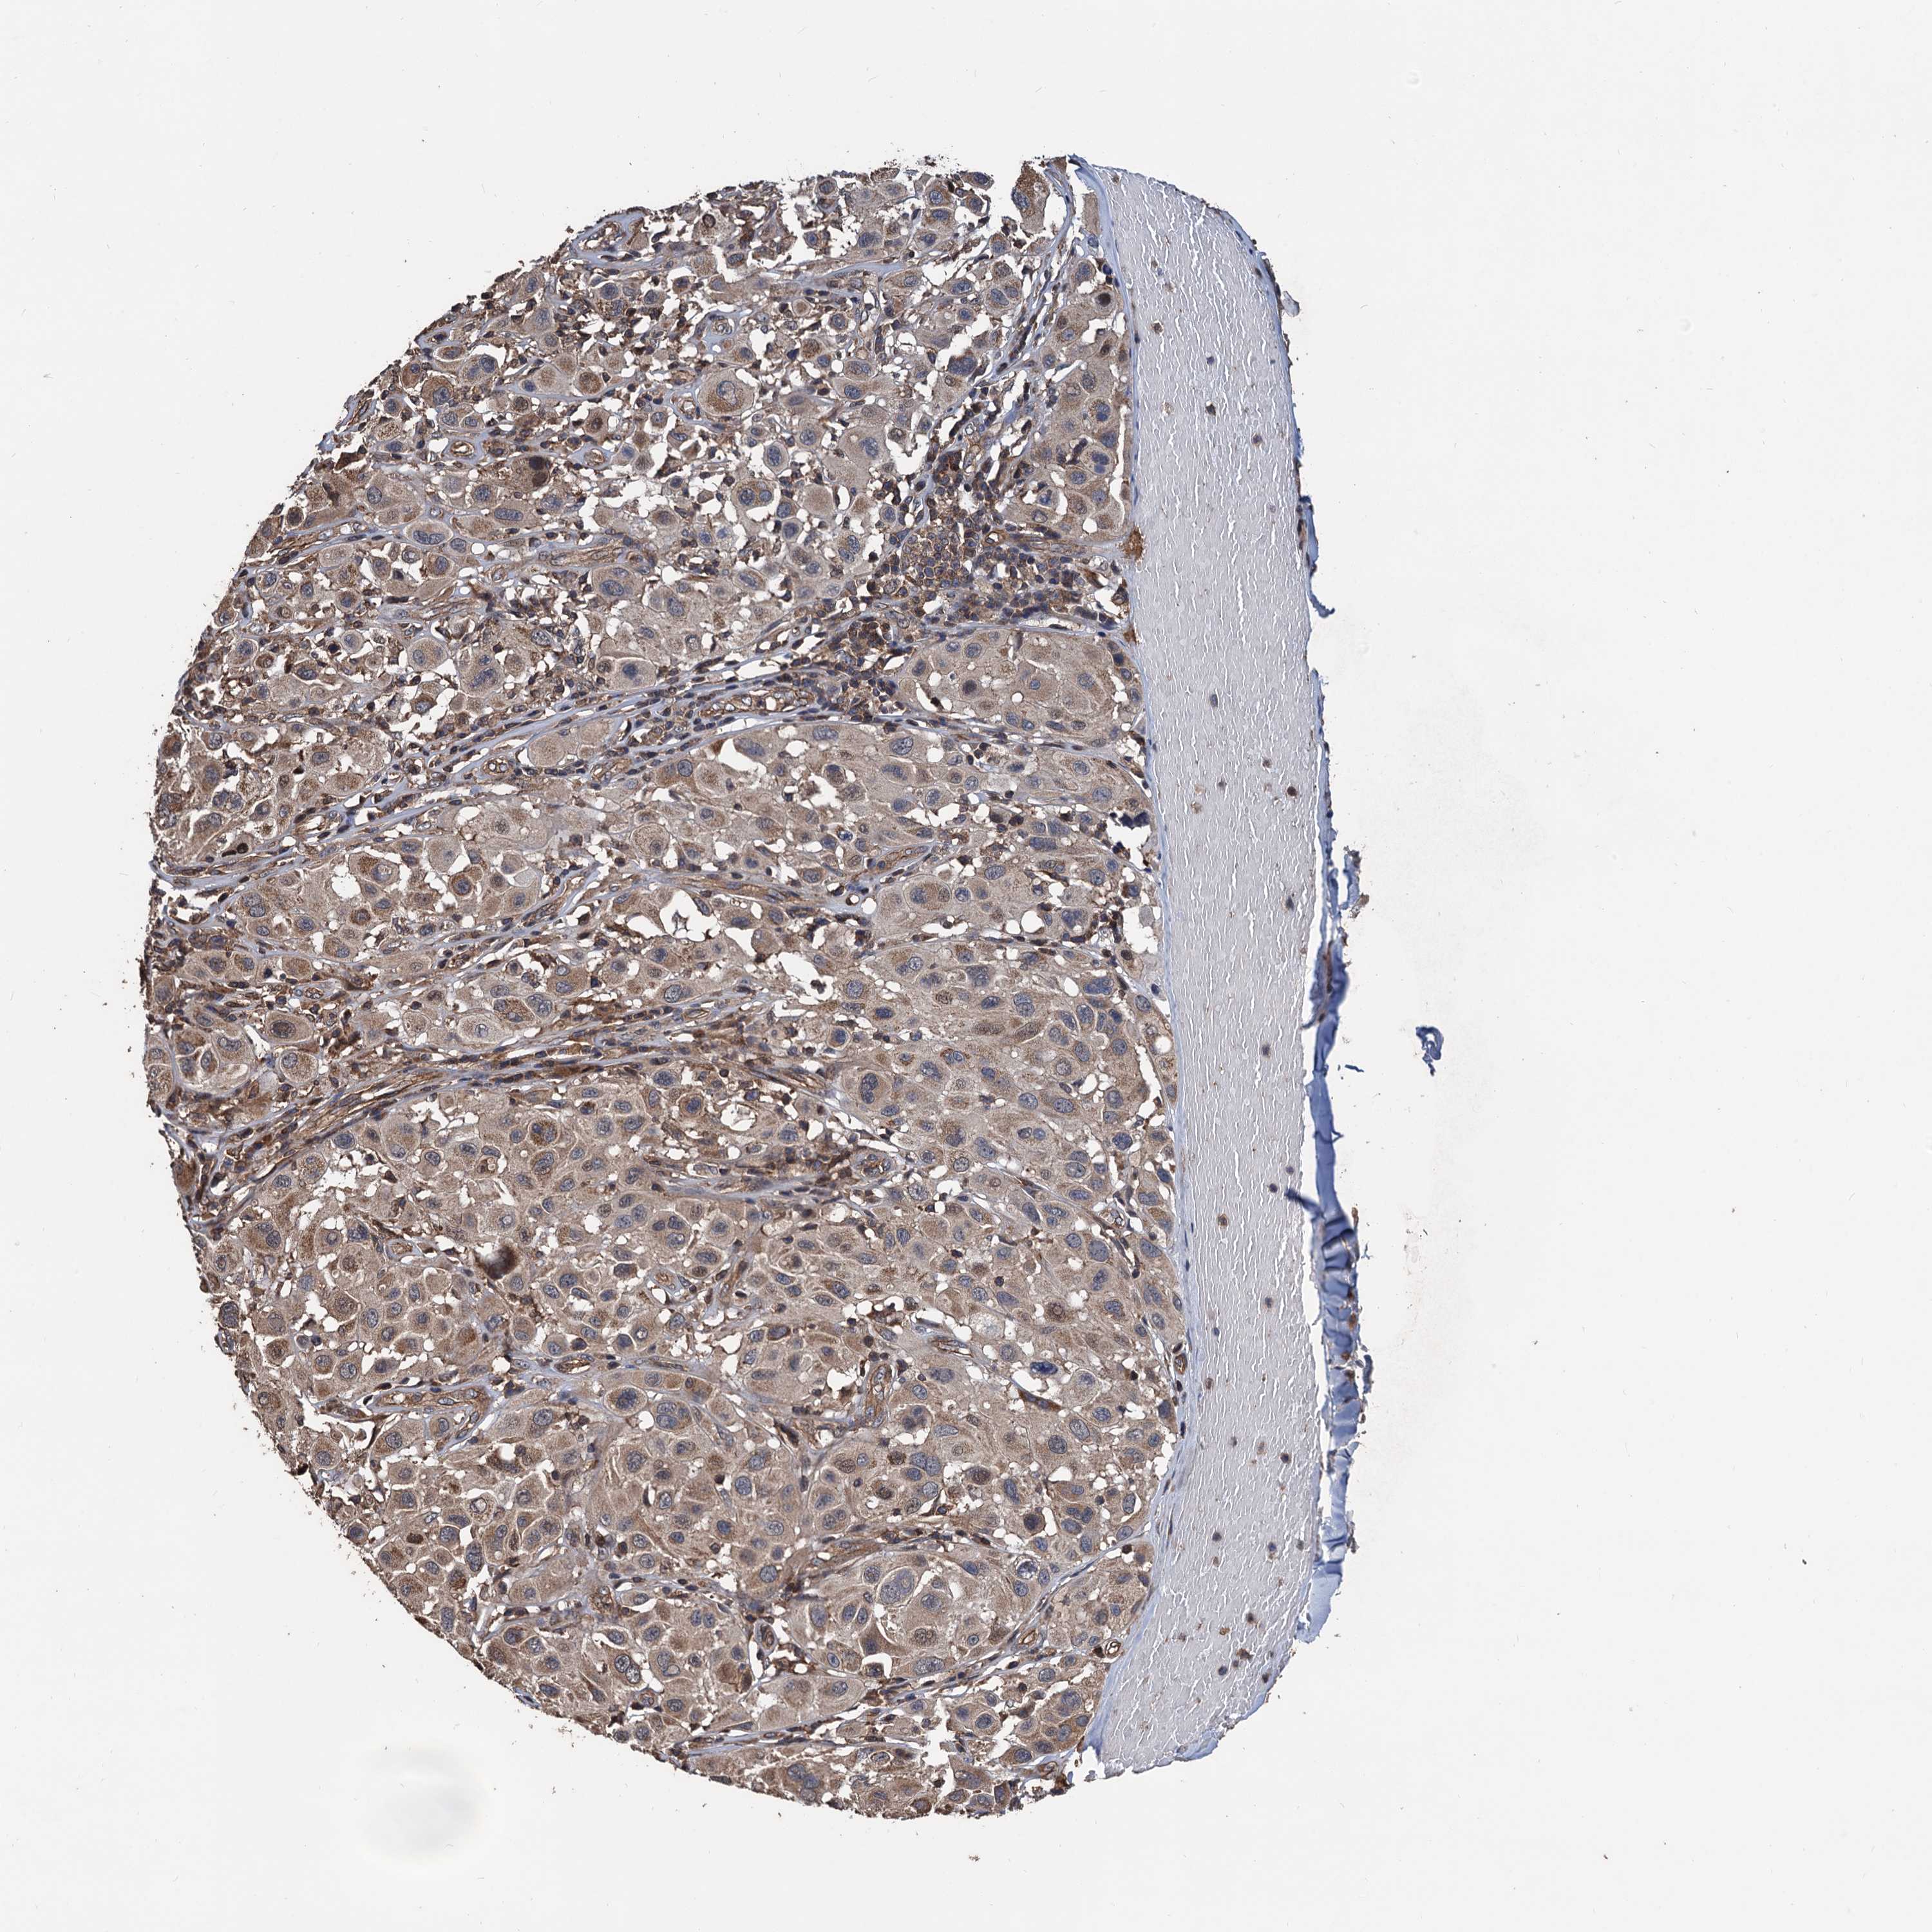

MELANOMA - Protein expressioni

A mouse-over function shows sample information and annotation data. Click on an image to view it in a full screen mode. Samples can be filtered based on level of antibody staining by selecting one or several of the following categories: high, medium, low and not detected. The assay and annotation is described here.

Note that samples used for immunohistochemistry by the Human Protein Atlas do not correspond to samples in the TCGA dataset.

Antibody stainingi

Antibody staining in the annotated cell types in the current human tissue is reported as not detected, low, medium, or high, based on conventional immunohistochemistry profiling in selected tissues. This score is based on the combination of the staining intensity and fraction of stained cells.

Each image is clickable and will lead to virtual microscopy that enables deeper exploration of all samples and also displays staining intensity scores, fraction scores and subcellular localization as well as patient and tissue information for each sample.

Antibody HPA040905

Antibody HPA041089

Staining

High

Medium

Low

Not detected

Intensity

Strong

Moderate

Weak

Negative

Quantity

>75%

75%-25%

<25%

None

Location

Nuclear

Cytoplasmic/membranous

Cytoplasmic/membranous,nuclear

Malignant melanoma, NOS

Malignant melanoma, Metastatic site